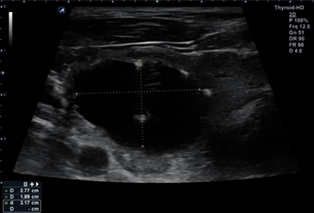

At one month follow-up, the patient noted

significant improvement in neck discomfort. The patient was seen in follow up

at three and six months. At twelve-month follow-up of RFA the nodule remains

stable to decreased in size to approximately 10 mL, significantly decreased in

size by more than 95% from baseline status post RFA and PEI (Figure 2). His

thyroid function tests remained normal. Discussion was made regarding repeat

intervention, but since the patient was so pleased with his status, the

decision was made to re-evaluate in one year with repeat ultrasound.

a)

Photo

b) Ultrasound image – AP and transverse view

c)

Ultrasound image – lateral view

Figure 2: Images one-year post-PEI

and RFA